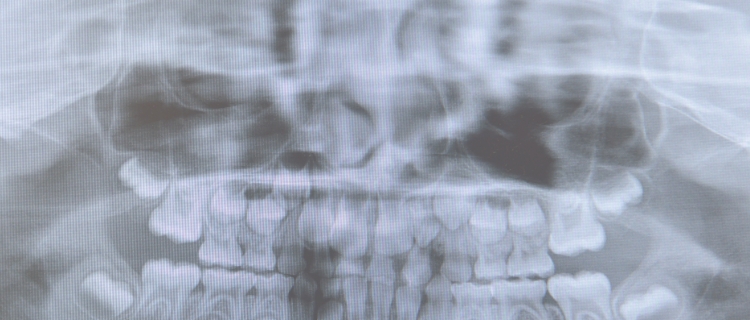

笑い声いっぱいの生活をしていきたい。健康な体はしっかり食べることが基本。そして体中に栄養を送ること。そのためには、きちんとした咬合でしっかり咀嚼すること。

矯正歯科治療は、自分の歯で最良の咬合を作っていくことです。

歯の機能は、食べ物をしっかりかみ砕いて、その食べ物を、飲み込んで体に栄養を送るという重要な役目があります。また、楽しくお話しする時にも歯は必要であり、楽しいお話をもっともっと楽しくするのはあなたのキレイな笑顔です。

キレイな歯並びは、あなた自身とまわりの人たちみんなをしあわせにする大事なものだと思ってください。歯並びのこと、噛み合わせのこと、歯のこと、気になることをご相談ください。